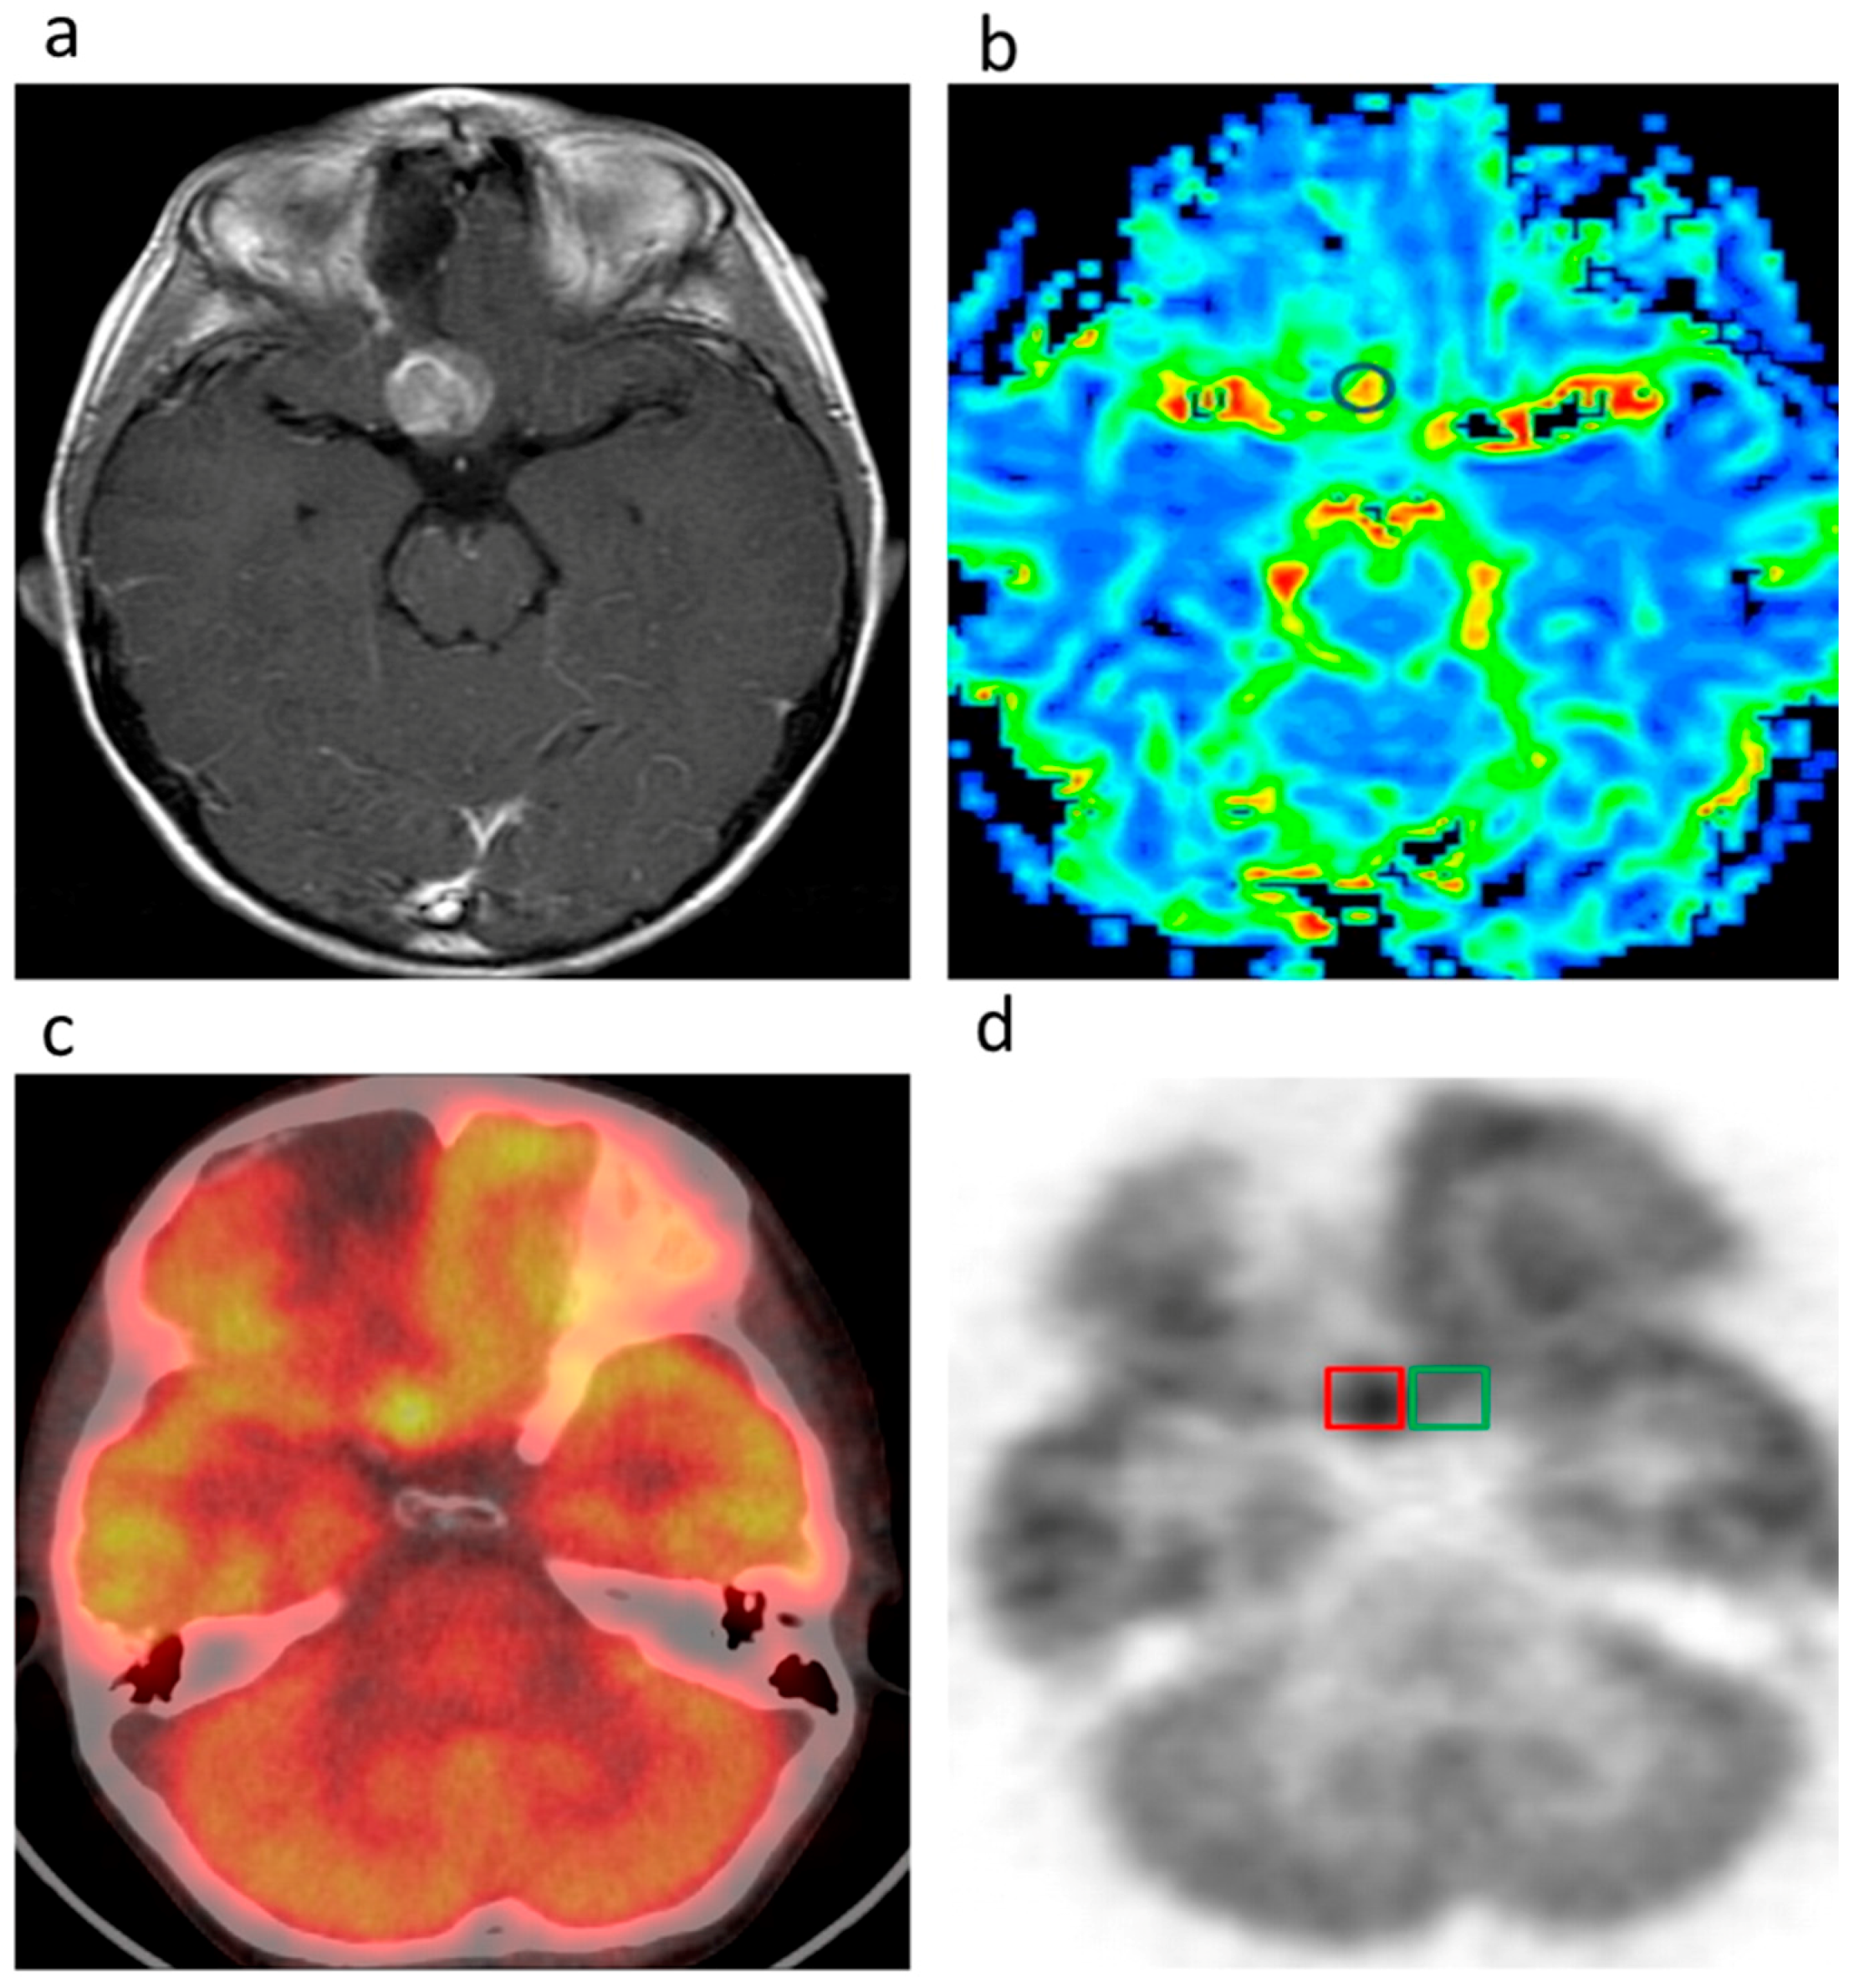

- Wright, E.A.; d'Esterre, C.D.; Morrison, L.B.; Cockburn, N.; Kovacs, M.; Lee, T.Y. Absolute cerebral blood flow infarction threshold for 3-h ischemia time determined with CT perfusion and 18F-FFMZ-PET imaging in a porcine model of cerebral ischemia. PLoS ONE 2016, 11, e0158157. [Google Scholar] [CrossRef] [PubMed]

| 5 | Fluoroflumazenil | PET-CT | Cerebral blood flow during heart attacks | Wright et al. [22] |